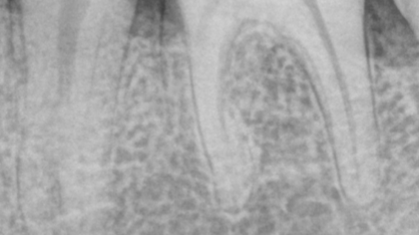

Caso clínico del doctor Marc Llaquet de una reendodoncia del diente 2.4 instrumentado con las limas RetreatAll® para…